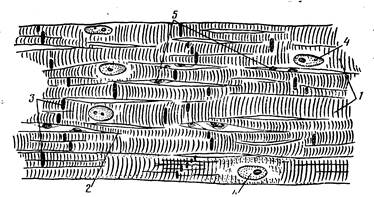

Миокард образован сердечной мышечной тканью, в которой различают две разновидности — рабочую и проводящую. Основная масса миокарда представлена рабочей мышечной тканью, состоящей из сократительных клеток — сердечных миоцитов, важнейшей морфологической особенностью которых являются совершенные в структурном и функциональном отношении аппараты крепления их друг с другом. Вследствие того что миоциты прочно соединены своими концами и образуют многочисленные анастомозы, в миокарде сформирована единая структурно-функциональная клеточная сеть. При световой микроскопии зоны контакта миоцитов имеют вид одиночных темноокрашивающихся прямолинейных или ступенчатых полосок, расположенных перпендикулярно длинной оси клетки, которые получили название вставочных дисков (рис. 198).

Рис. 198. Схема строения участка рабочей мышечной ткани миокарда:

1 — миокардиоциты; 2 — анастомозы; 3 — вставочные участки; 4 — ядра миокардиоцитов; 5 — ядра эндотелия капилляров.